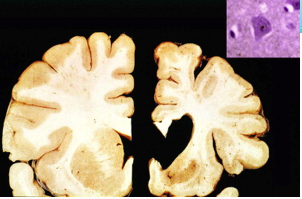

What is shown in this image?

Parkinson disease:

Lewy bodies are present in dying neurons mainly in the dopaminergic areas (e.g. substantia nigra). The loss of pigmented neurons leads to pallor of the substantia nigra. Lewy bodies contain α-synuclein